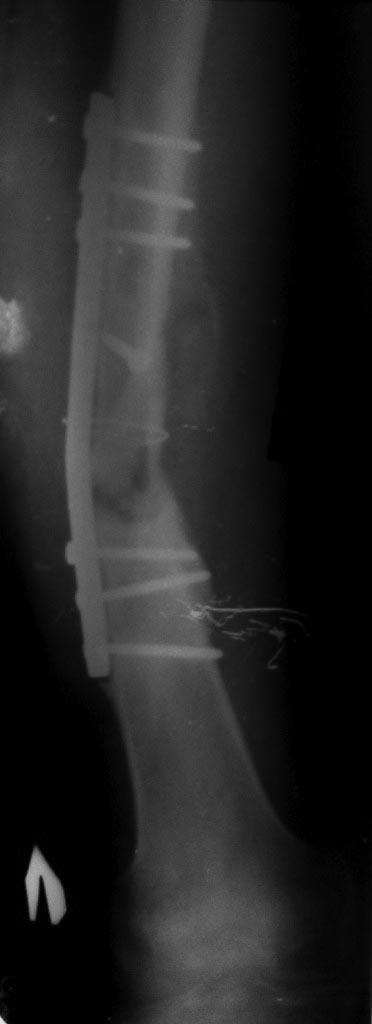

Доброго времени суток! Лечение нереактивного псевдоартроза: адаптация концов отломков, костная пластика и стабильная фиксация. По состоянию костей на настоящее время требуется блокируемая пластина. В дальнейшем приступите к разработке коленного сустава. Никакой аппарат Вам не даст в полной мере разработку сустава по понятным причинам. Большое спасибо!

От ЧКДО больной котегорически отказывается, я тоже полагаю, что лучше ставить блокируемую пластину.

Можно так предложить, что больной совсем откажется от оперативного лечения - я иногда так делаю. Ну уж если заранее решили пластину, видно, так тому и быть, только не забудьте побольше винтов поставить! Кости-то порозные. Заранее подумайте где, что бы не было некроза кожи. Тогда точно придется откапывать труды Гавриила Абрамовича. (Он и не догадывался, что его методика почему то вдруг окажется временной!)

Согласен с Андереем Кияночкиным. Вопрос давно решенный: с биологией голени все в порядке, потенциал к сращению не утерян . После этапной постепенной коррекции деформации любой метод СТАБИЛИЗАЦИИ перелома приемлем и функционален: БИОС,АВФ,LCP,DCP.